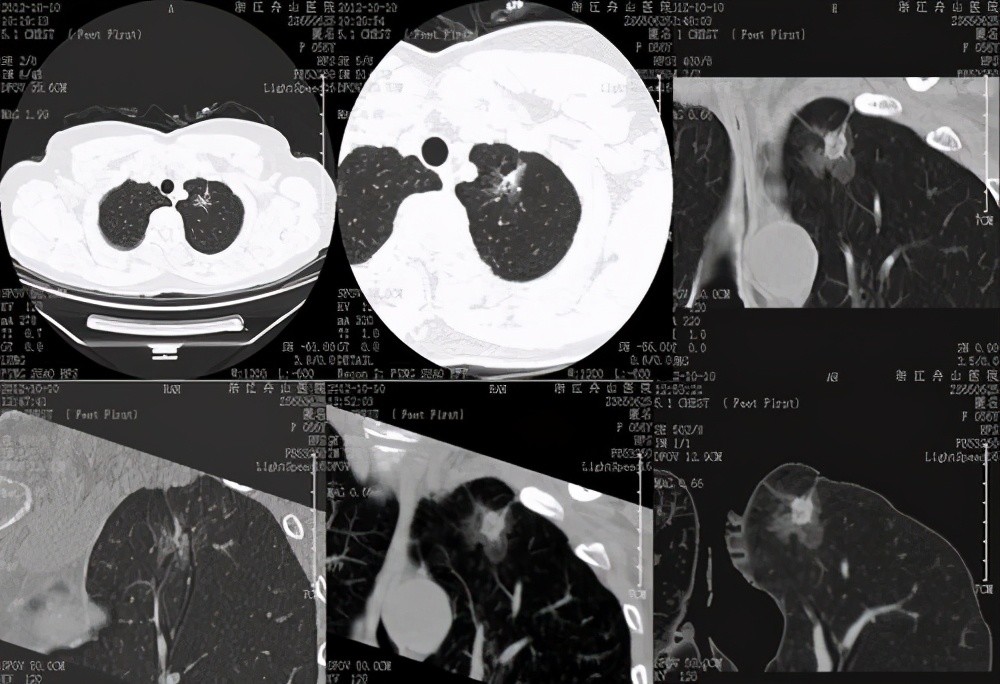

常规胸部CT扫描由于视野大、层厚较厚 , 不能全面观察肺结节影像特征 。 靶扫描又称放大扫描、感兴趣区扫描 , 是针对肺部

靶扫描可以更全面、多方位、更直观地观察病灶的形态、特征 , 观察病灶边缘、中心结构 , 然后通过计算机处理和医生的经验去发现有价值的诊断线索 , 从而得出更为准确的结论 。 靶扫描通过提高空间分辨率 , 更好地显示肺结节病变特征 , 为肺内结节的定性诊断提供更多的依据 。

肺部充满气体 , 属于具有良好自然对比的脏器 , 但肺脏不停地呼吸运动 , 做CT时容易受到呼吸运动的影响 , 靶扫描使用小范围、薄层技术采集到的小体积像素对呼吸运动伪影具有几何放大的作用 , 也就是说极大减少了呼吸运动伪影 。

【结节|肺结节为何要做靶扫描?可更加具体地提供结节的细节,诊断更准确】不少病人问 , 我查出肺结节 , 需不需要做增强CT , 增强CT就是往血管里打造影剂然后扫描 。 增强扫描有两个意义:一是如果病灶血供丰富 , 注射造影剂后病灶有强化 , 从而判断其富血供 , 考虑恶性可能大;另一个是纵隔内增强可区分出血管与淋巴结 , 从而判断有无肿大淋巴结 , 特别是是不是存在淋巴结转移的可能性 。 然而对于1~2公分的肺结节 , 尤其是有许多磨玻璃成份时 , 增强CT强化程度可能比较有限 , 提供的信息相较于CT平扫多不了多少 。 而此时如果进行靶扫描 , 则能够更有利于对细小病灶进行观察和判断 。